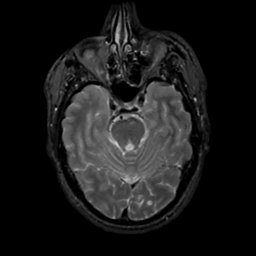

MR Study #3, February 24, 1991 -- Slice #16

[Home][Help][Clinical][Tour 1][Tour 2] Slice 16